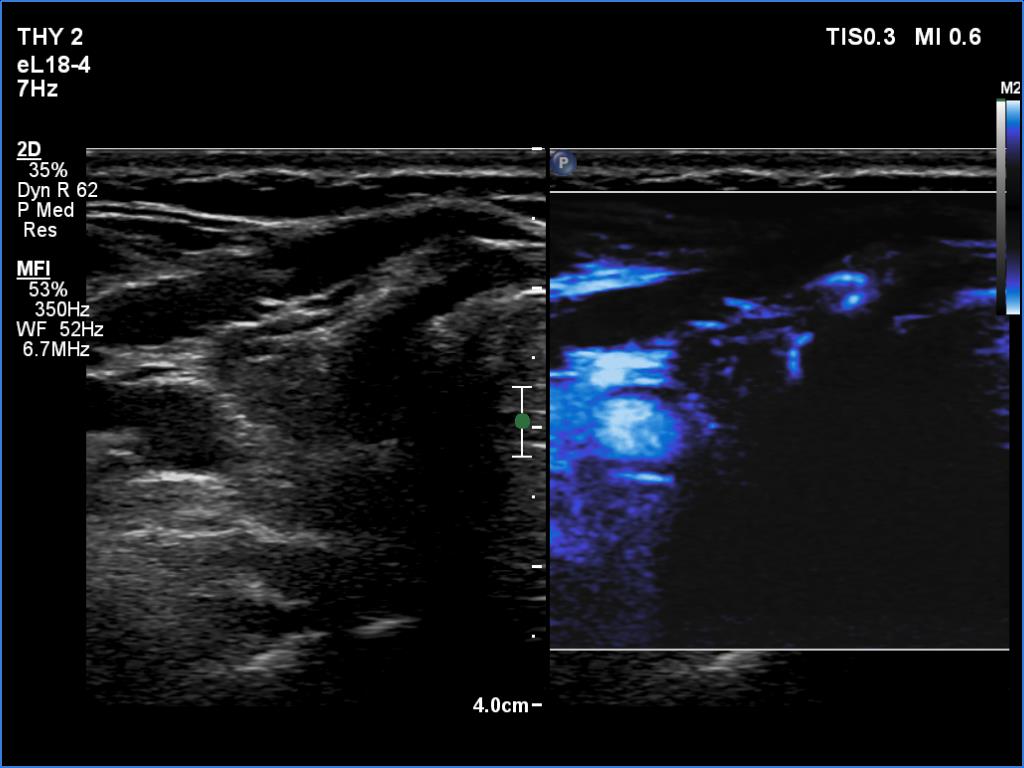

Right lobe, longitudinal scan

Right lobe, transverse scan, mircoflow imaging. There are only a few vessels within the lobe.